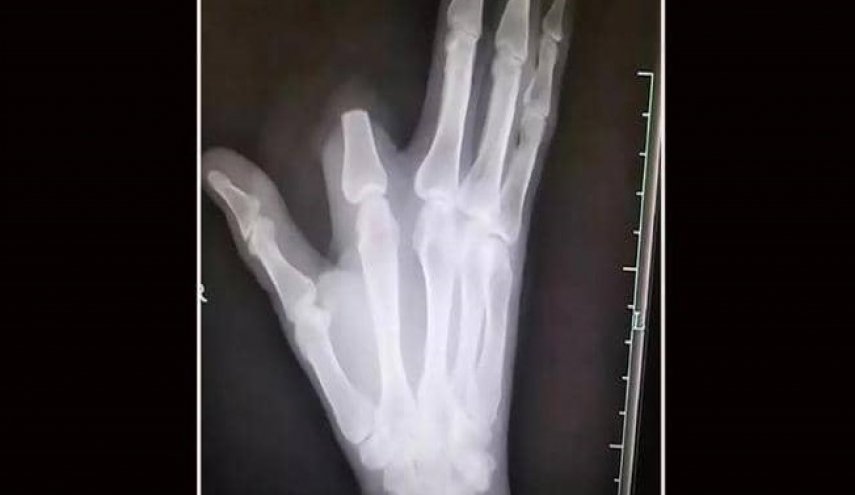

بينما كان يعمل في أحد جبال الصين، تعرض رجل في الستينيات من عمره إلى لدغة في أحد أصابع يده، من أفعى تحركت خلسة دون أن يشعر بوجودها.

وظن الرجل أن لدغة الأفعى شديدة السمية وقد تؤدي إلى موته فورا، فسارع إلى قطع إصبعه بسكين كان بحوزته من أجل "إنقاذ حياته"، بحسب ما أوردت شبكة "فوكس نيوز".

لكن الرجل الذي اتخذ القرار المؤلم بقطع إصبعه، لم يكن مضطرا لفعل ذلك، لأن سم هذا النوع من الأفاعي ليس قاتلا على الإطلاق، بل إنه يستخدم في تحضير علاجات للمفاصل والعظام.